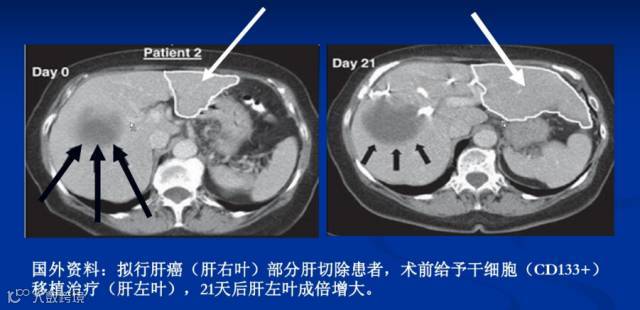

2、干细胞移植为肝硬化的治疗提供了新的手段:

基础研究:干细胞作为一种具有横向分化能力的多能干细胞,近年来大量研究表明在合适的培养条件下其在体内外均可以向肝细胞分化。